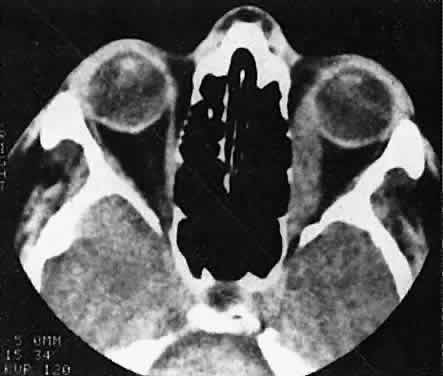

CT discloses a single or multilobulated mass, which represents only the blood cyst portion of the tumor (Fig. 14). Individual lobules may have different radiodensities depending on the presence of clots or liquefied blood within each cyst (Fig. 15). A generalized increase in orbital dimensions suggests a long-standing, probably congenital process. Echography may help differentiate the cystic components of lymphangioma from cellular rhabdomyosarcoma. Echography shows the blood cysts to be acoustically inactive spaces, with extremely low internal reflectivity (Fig. 16). Clots within the cysts can increase internal heterogeneity, however. MRI has virtually eliminated the need for diagnostic biopsy in this condition, because of its ability to show differing magnetic properties of suspended, degrading blood products (Fig. 17).

Fig. 14. CT appearance of hemorrhagic cysts in two different cases. A. A single intraconal cyst compressing the optic nerve. B. Multilobulated contiguous cysts. Intervening, nonexpanded segments are microscopic and not detectable with imaging studies.

Fig. 15. Lymphangioma with heterogeneous radiodensities. Clots were found in the denser anterior blood cysts, whereas the most posterior cyst had liquid contents.